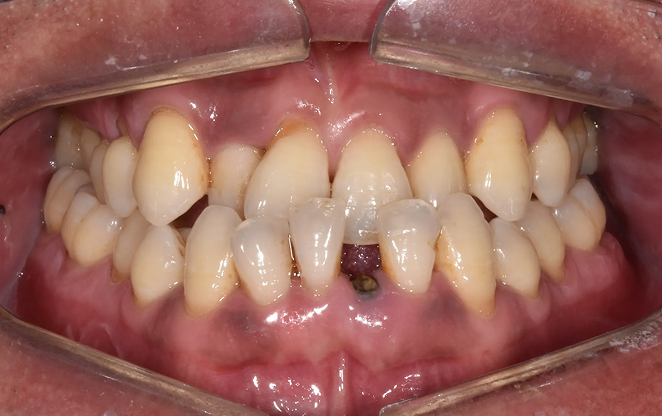

Before

After

비보철 교정은 치아를 뽑거나 보철물을 사용하지 않고,

내 치아 그대로의 아름다움을 지켜가며 교정하는 방법입니다.

불필요한 보철 없이 치아의 배열을 조정해, 자연스럽고 건강한 치아와

균형 잡힌 미소를 찾아가는 과정입니다. 자연스러움 속에서 완성되는

건강한 미소, 비보철 교정으로 그 여정을 시작하세요.